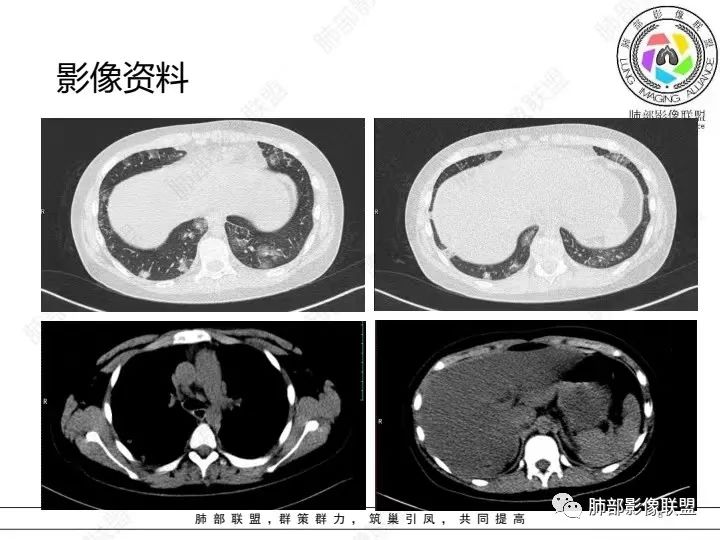

【病例】血源性金黄色葡萄球菌性肺炎1例CT影像

1.男性少年儿童,外伤后髋部疼痛,畏寒发热、咳嗽、呼吸困难。

休克血压。CRP、PCT明显升高。血气为代谢性酸中毒、呼吸性碱中毒。

2.影像上肺多发混合密度片影,随机分布,胸膜下分布优势,病灶边界大多隐约可辨,偏柔和,动脉血管影穿行,未见钙化、液化空洞、或明确气囊影,未见树芽征。

3.双侧胸腔未见积液。双肺门及纵隔未见增大淋巴结。

4.肝左右叶密度减低,未见结节影、块影或液化区。